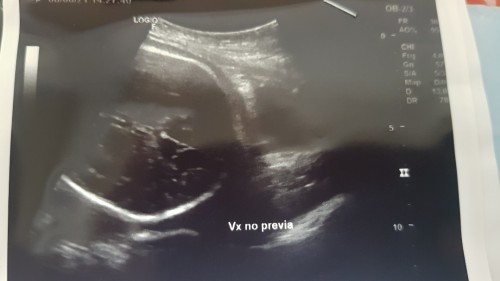

รกเกาะต่ำ ไม่ลอย

แบบนี้ถือว่าอันตรายมั้ยคะ รกเกาะต่ำ ไม่ลอย 36+2 ค่ะ #ขอคำแนะนำหน่อยค่ะ #ใครมีประสบการณ์

เสี่ยงคลอดก่อนกำหนดได้ค่ะ ทำตามคำแนะนำหมอ รกสามารถลอยขึ้นมาได้